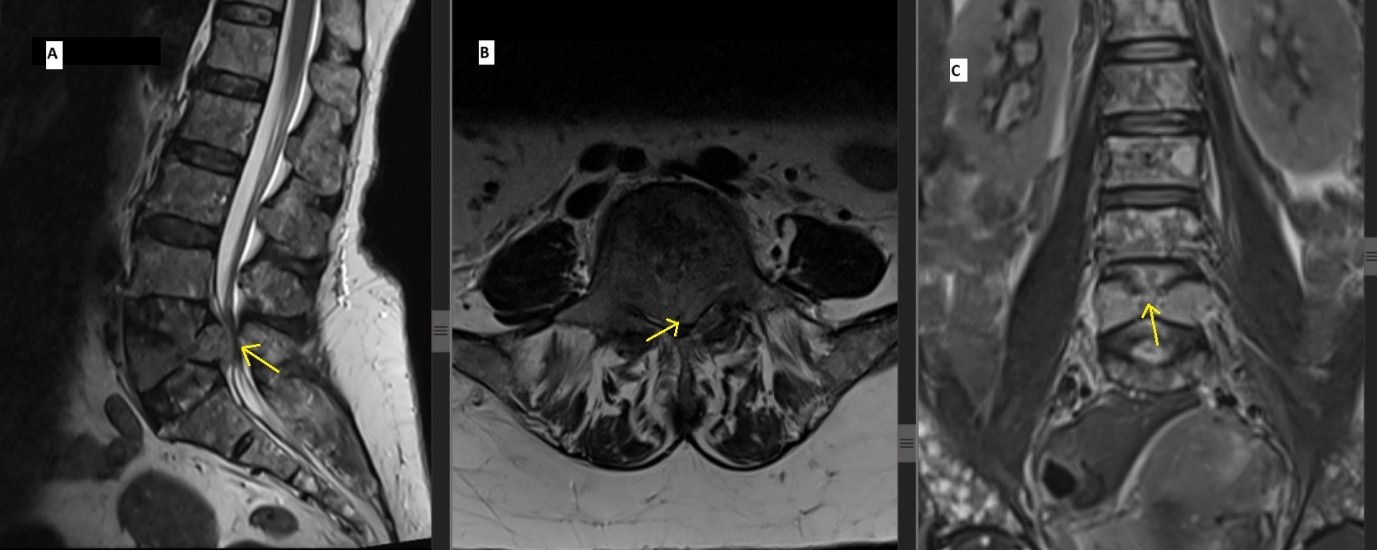

Magnetic resonance imaging (MRI) of the spine demonstrated altered heterogeneous signal intensity involving the marrow and a compression fracture L5, with reduced vertebral height was causing significant spinal canal stenosis and cauda equina compression. These findings were suggestive of a pathological fracture due to MM (Fig. 3).

Figure 3: Magnetic resonant images showing L5 vertebral compression fracture with decreased vertebral height is seen causing significant stenosis of spinal canal and compression of cauda equina (a) Sagital T2 weighted image, (b) Axial T2 weighted image, (c) Coronal T2 weighted image).